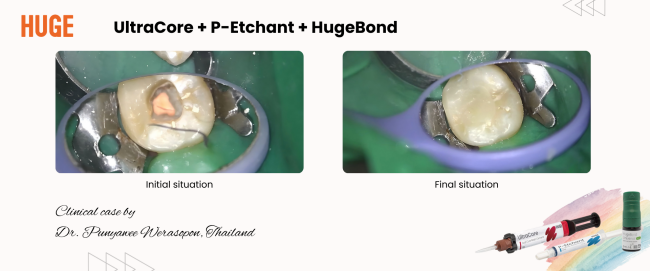

Reliable Posterior Core Build-up with UltraCore: Clinical Case on Tooth #37

Clinical Case: Direct Core Build-up on Tooth #37

This case was contributed by Dr. Punyawee Werasopon, DDS, M.Sc., a board-certified endodontist in Thailand.

A 30-year-old male patient came for restorative treatment after completing root canal therapy on tooth #37. The tooth had minimal structural loss, and the remaining dentin walls provided adequate retention for core build-up material.

An adhesive core build-up was performed using phosphoric acid etch and rinse, followed by light-cured universal bonding and a dual-cured resin core material.

The tooth is now ready for a cuspal-coverage restoration as the next step to restore full function and long-term durability.